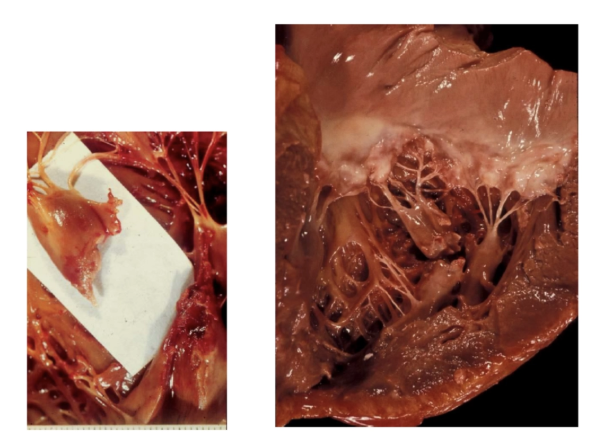

Hemopericardio: acumulación de sangre, principalmente por rotura cardiaca

Mixoma

Rabdomioma

Fibroelastoma papilar